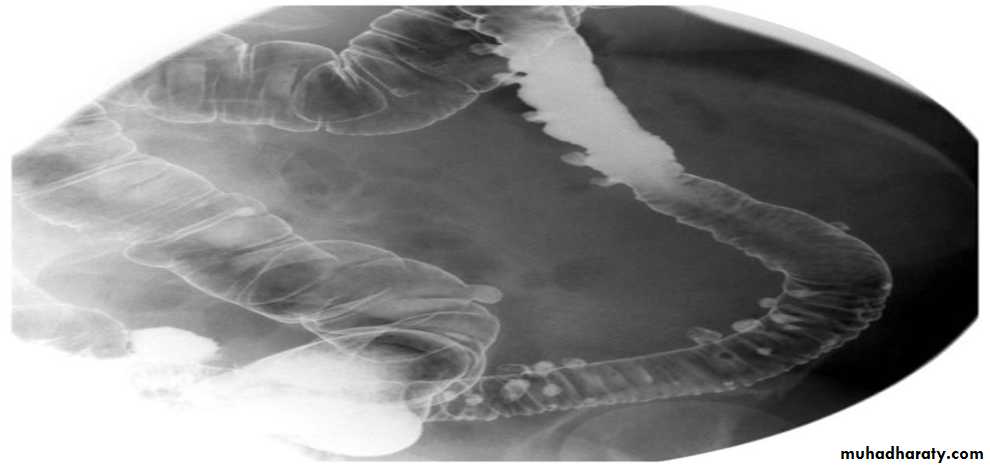

Barium enema

A: caecumB: ascending colon

C: transverse colon

D: descending colon

E: sigmoid colon

HF: hepatic flexure

SF: splenic flexure

F: terminal ileum

F